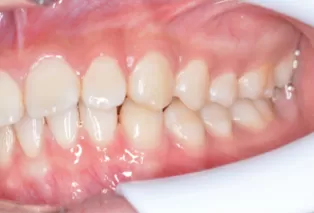

Photos intra-orales

teeth straightening aligners 4

teeth straightening aligners 5

teeth straightening aligners 6

teeth straightening aligners 7

teeth straightening aligners 8